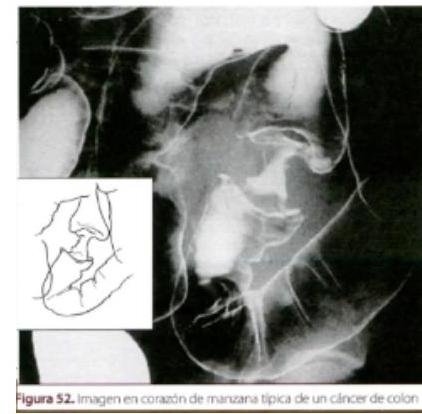

# CÁNCER COLORRECTAL ## DEFINICIÓN El cáncer colorrectal (CCR) o adenocarcinoma colorrectal es un tumor **maligno** que se origina dentro de las paredes del intestino **grueso**. Incluye los segmentos: ciego, colon ascendente, colon transverso, colon descendente, sigmoides y recto. El grupo de CCR **NO** incluye los tumores en los tejidos del ano o del intestino delgado. Los **adenomas** son tumores **benignos** epiteliales que se consideran lesiones **precancerosas**; pueden tener diferentes grados de **displasia** o diferentes características **histológicas**: tubular, tubulovellosos, asociadas con el aumento de potencial de **malignidad**.  La división la marca el ángulo esplénico. ## EPIDEMIOLOGÍA - **Mutaciones genéticas** involucradas: **MLH1** y **MSH2**. - El CCR es más frecuente en **FAMILIARES DE PRIMER GRADO** con antecedentes. Existen dos **Síndromes Genéticos** que predisponen: 1. **Poliposis Adenomatosa Familiar (PAF)** - riesgo 60-90 % a. **Síndrome de Gardner**: Cáncer de Colon + Cáncer Papilar de Tiroides b. **Síndrome de Turcot**: Cáncer de Colon + Tumores Malignos del SNC. 2. **Cáncer Colorrectal Hereditario NO Asociado a Poliposis (CCHNP)** - Síndrome de Lynch ## CLASIFICACIÓN DEL RIESGO ## RIESGO BAJO - > 50 años (en personas de raza negra > 45 años) - Sin historia personal de pólipos o CCR - Sin historia personal de EII - Sin historia familiar de CCR: - Familiar de 1^{\text{a}} grado diagnosticado antes de los 60 años - Dos familiares de 1^{\text{a}} grado diagnosticados a cualquier edad - Sin historia familiar de Pólipos Adenomatosos: - Familiar de 1^{\text{a}} grado diagnosticado antes de los 60 años ## RIESGO INTERMEDIO - Pólipos de colon adenomatosos y hamartomatosos - EII con 10 o más años de evolución ## RIESGO ALTO - Familiar de 1^{\text{a}} grado con **Cáncer Hereditario Colorrectal** - Historia familiar relacionada con **CCHNP** - Cánceres extracolónicos asociados: endometrio, ovario, gástrico, intestino delgado # CLASIFICACIÓN 1. Esporádico 2. Hereditario Polipoide 3. Hereditario No Polipoide (Lynch I y II) ## CÁNCER COLORRECTAL NO POLIPOIDE HEREDITARIO ## Síndrome de Lynch II 1. Autosómico dominante 2. Inicio temprano (media 46 años) 3. Múltiple (sincrónico o metacrónico) 4. Más común en colon proximal (antes del ángulo esplénico) 5. Inestabilidad microsatelital 90 % ## Riesgo de Síndrome de Lynch II - con estos criterios. Amsterdam I y II - Tres familiares con cáncer de colon o cánceres asociados a **CCHNP**; uno de ellos debe ser pariente en primer grado de los otros dos - Dos generaciones sucesivas afectadas - Al menos un caso diagnosticado antes de los 50 años Criterios de Bethesda - Persona con dos tipos de cáncer asociados a **CCHNP** - Una persona con cáncer de colon y un pariente en primer grado con cáncer de colon y/o cánceres asociados a **CCHNP** (<44 años) y/o adenomas (<40 años) - Persona con cáncer de colon o endometrio antes de los 45 años - Persona con cáncer de colon en lado derecho que presente bajo grado de diferenciación antes de los 45 años # TAMIZAJE La detección **oportuna** plantea estrategias para la **población asintomática** con un **riesgo promedio** de **CCR**. Se considera que estas pruebas pueden incrementar el número de **falsos positivos** con el consecuente impacto en la calidad de vida y la necesidad de realizar estudios **invasivos**. ## BÚSQUEDA DE SANGRE OCULTA EN HECES BASADA EN GUAYACO Es el estudio de **ESCRUTINIO** EN **POBLACIÓN DE RIESGO BAJO** al no ser **invasiva**. **Accesible**. - Realizar **anualmente** a partir de 50 años y realizar **colonoscopia** en caso de resultado positivo. - Si se toman dos muestras diferentes se aumenta la sensibilidad. - Estudios han demostrado que la prueba puede reducir la **mortalidad** por **CCR** en 15-33 %. - **NO** es efectiva en la detección de pólipos **precancerosos** y en menores de 1 cm. Previo al examen: Evitar **AINES**, **ASA**, Carne Roja, **Vitamina C**. ## BÚSQUEDA DE SANGRE OCULTA EN HECES CON INMUNOHISTOQUÍMICA Detecta **CCR** y pólipos que sangran periódicamente. Esta prueba detecta **sangre oculta en heces** utilizando uno o más **anticuerpos monoclonales**. Ventajas: disponible en el entorno clínico, **no implica riesgo**, no produce **falsos negativos** por **Vitamina C**, **no requiere restricción en la dieta** (como en el guayaco). Desventajas: Requiere **adhesión** para realizarse anualmente. Si es positivo - **Colonoscopia**. ## COLONOSCOPIA - **Riesgo Intermedio** - cada 5 años - **Riesgo Alto** - cada 2 años (a partir de los 18 años de edad). # CLÍNICA - Dolor abdominal - Cambio de hábitos intestinales - Pérdida de peso - Sangrado rectal: Rectorragia, hematoquezia o melena - **Anemia microcítica hipocrómica** (sin etiología aparente) ## PÓLIPOS Y CÁNCER ## PÓLIPOS NEOPLÁSICOS (ADENOMATOSOS) - Adenomas tubulares (5 % se **malignizan**) - el más frecuente - Adenomas tubulovellosos (20-25 % se **malignizan**) - **ADENOMAS VELLOSOS** (35-40 % se **malignizan**) - Los más malignos ## PÓLIPOS NEOPLÁSICOS NO EPITELIALES - Leiomioma, lipoma, neurofibroma, hemangioma ## PÓLIPOS NO NEOPLÁSICOS - **Hamartomatosos** (**Sx Cowden**, **Sx Peutz-Jeghers**) - Inflamatorio - Hiperplásicos - Mucosos  Pólipo plano o invertido. Carcinoma de novo.  # DIAGNÓSTICO ## **GOLD STANDARD**: **COLONOSCOPÍA** + **TOMA DE BIOPSIA** PARA **HISTOPATOLOGÍA** - Este estudio es **invasivo** y permite **visualizar** en forma directa toda la extensión del colon. - Existe un **riesgo de perforación** de 2/1.000. Indicada en: - **Riesgo Bajo** con prueba de sangre oculta en heces **positiva** - realizar cada 10 años. - **Riesgo Intermedio** y **Alto**, independientemente del resultado de sangre oculta en heces - intervalo dependiendo de cada caso. ## **SIGMOIDOSCOPÍA FLEXIBLE** - Detecta el **CCR** y los pólipos **adenomatosos** al nivel de la inserción del endoscopio. - Es un estudio **invasivo** que permite la **toma de biopsia** o **polipectomía**. - No requiere **sedación** y el riesgo de perforación es **menor**. - Limitante - **EXAMINA SOLAMENTE COLON IZQUIERDO**. Indicado en: Pacientes con Lesiones sospechosas en **Colon Izquierdo** sin factibilidad de realizar **Colonoscopía**. ## **COLON POR ENEMA DOBLE CONTRASTE** Se sugiere en **Riesgo Bajo** con sangre oculta en heces **positiva** en los cuales no se pueda realizar los dos estudios previamente **mencionados**. **Riesgo Intermedio** y **Alto** asintomáticos que no se puedan realizar los previos. - **IMAGEN CLÁSICA EN "CORAZÓN DE MANZANA"**. ## **COLONOSCOPÍA VIRTUAL** Detecta pólipos **adenomatosos** y **CCR** con una **mínima invasión** de todo el colon  y similar precisión a la **Colonoscopía**. Indicado en: - Después de un examen **incompleto** o **colonoscopía diagnóstica** - Pacientes que no pueden suspender **anticoagulación** - **Rechazo** de **colonoscopía** - **Falta de disponibilidad** **SEGUIMIENTO DE INDIVIDUOS ASINTOMÁTICOS**: | Colonoscopía | Cada 10 años | | :---------------------- | :-- | | Sigmoidoscopía flexible | Cada 5 años | | Colon por enema doble | Cada 5 años | | Colonoscopía Virtual | Cada 10 años | **Antígeno Carcinoembrionario**: Solicitar antes de Qx para posterior darle seguimiento. # TRATAMIENTO Los principios del tratamiento utilizan **resección quirúrgica** y **quimioterapia coadyuvante** para la **enfermedad residual**. ## REFERENCIA Se enviará de la consulta familiar a segundo nivel (MI o Gastroenterología) si presenta lo siguiente: 1. Dolor abdominal, cambio de hábito intestinal y pérdida de peso 2. Edad menor de 40 años con **AHF de Cáncer de Colon** 3. Edad mayor de 50 años 4. **AHF de primera línea con Cáncer de Colon** 5. **Anemia Microcítica e hipocrómica** sin causa aparente ## Algoritmo para el escrutinio y diagnóstico del **Cáncer Colorrectal** de acuerdo a su riesgo  # Vigilancia de PÓLIPOS COLÓNICOS - No **pólipos** - Cada 10 años - **Pólipos hiperplásicos** <10 mm - Cada 10 años - 1-2 **adenomas** <10 mm - Cada 5-10 años - 3-10 **adenomas** - Cada 3 años - >10 **adenomas** - Cada <3 años - **Adenoma** >1 cm - Cada 3 años - **Adenoma velloso** - Cada 3 años - **Adenoma** con **displasia de alto grado** - Cada 3 años

# CÁNCER DE COLON-RECTO ## DEFINICIÓN El cáncer colo-rectal (CCR)o adenocarcinoma colo-rectal es un tumor maligno que se origina dentro de las paredes del intestino grueso, incluye los segmentos: ciego, colon ascendente, colon transverso, colon descendente, sigmoides y recto. El grupo de CCR NO incluye los tumores en los tejidos del ano o del intestino delgado. Los adenomas son tumores benignos epiteliales que se consideran lesiones precancerosas; pueden tener diferentes grados de displasia o diferentes características histológicas: tubular, túbulo-vellosas, asociadas con el aumento de potencial malignidad.  La división la marca el ángulo esplénico ## EPIDEMIOLOGÍA - Mutaciones genéticas involucradas: MLH 1 y MSH 2 - El CCR es más frecuente en FAMILIARES DE PRIMER GRADO con antecedentes. Existen dos Síndromes Genéticos que predisponene: 1. Poliposis Adenopatosa Familiar (PAF) - riesgo 60-90 % a. SíNDROME DE GARNER: Ca Colon + Ca Papilar Tiroides b. SíNDROME DE TURCOT: Ca Colon + Tumores Malignos del SNC. 2. Cáncer Colo-Rectal Hereditario NO Asociado a Poliposis (CCHNP) - Síndrome de Lynch ## CLASIFICACIÓN DEL RIESGO ## RIESGO BAJO - +50 años (negros +45 años) - Sin historia personal de pólipos o CCR - Sin historia personal de Ell - Sin historia familiar de CCR: - Familiar 1^{\text {a }} grado con Dx antes 60 años - Dos familiares 1^{\text {a }} grado Dx a cualquier edad - Sin historia familiar de Pólipos Adenomatosos: - Familiar de 1a grado dx antes de 60 años ## RIESGO INTERMEDIO - Pólipos de colon adenomatosos y hamartomatosos - Ell con 10 o más años de evolución ## RIESGO ALTO - Familiar 1a grado con Cáncer Hereditario Colo Rectal - Historia familiar relacionada a CCHNP - Cáncer extra colónico asociado: endometrio, ovario, gástrico, intestino delgado # CLASIFICACIÓN 1. Esporádico 2. Hereditario Polipoide 3. Hereditario No Polipoide (Lynch I y II) ## CÁNCER COLORECTAL NO POLIPODIE HEREDITARIO ## Síndrome de Lynch II 1. Autosómico dominante 2. Inicio temprano (media 46 años) 3. Múltiple (sincrónico o metacrónico) 4. Más común en colon proximal (antes de ángulo esplénico) 5. Inestabilidad microsatelital 90 % ## Riesgo de Sx Lynch II - con estos criterios. Amsterdam I y II - Tres familiares con cáncer de colon o cánceres asociados a CCHNP, uno de ellos debe ser pariente en primer grado de los otros dos - Dos generaciones sucesivas afectadas - Al menos un caso diagnosticado antes de los 50 años Criterios de Bethesda - Persona con 2 tipos de cáncer asociados a CCHNP - Una persona con cáncer de colon y un pariente en primer grado con cáncer de colon y/o cánceres asociados a CCHNP ( <44 años) y/o adenomas ( <40 años) - Persona con cáncer de colon o endometrio antes de los 45 años - Persona con cáncer de colon en lado derecho que presenten bajo grado de diferenciación antes de los 45 años # TAMIZAJE La detección oportuna plantea estrategias para la población asintomática con un riesgo promedio de CCR. Se considera que estas pruebas pueden incrementar el número de falsos positivos con el consecuente impacto en la calidad de vida y la necesidad de realizar estudios invasivos. ## BÚSQUEDA DE SANGRE OCULTA EN HECES BASADAS EN GUACAYO Es el estudio de ESCRUTINIO EN POBLACIÓN DE RIESGO BAJO al no ser invasiva. Accesible. - Realizar anualmente a partir de 50 años y realizar colonoscopia en caso de resultado positivo. - Si se toman dos muestras diferentes se aumenta la sensibilidad. - Estudios han demostrado que la prueba de puede reducir la mortalidad por CCR en 15-33 %. - NO es efectiva en detección de pólipos precancerosos y en menores de 1 cm . Previo al examen: Evitar AINES, ASA, Carne Roja, Viamina C. ## BÚSQUEDA DE SANGRE OCULTA EN HECES CON INMUNOHISTOQUÍMICA Detecta CCR y pólipos que sangran periódicamente. Esta prueba detecta sangre oculta en heces utilizando uno o más anticuerpos monoclonales. Ventajas: disponible en entorno clínico, no implica riesgo, no produce falsos negativos por Vitamina C, no requiere restricción en la dieta (como en el guayaco). Desventajas: Requiere adhesión para realizarse anualmente. Si es positivo - Colonoscopia. ## COLONOSCOPIA - Riesgo intermedio - cada 5 años - Riesgo alto - cada 2 años (a partir de los 18 años de edad). # CLINICA - Dolor abdominal - Cambio de hábitos intestinales - Pérdida de peso - Sangrado rectal: Rectorragia, hematoquezia o melena - Anemia microcítica hipocrómica (sin etiología aparente) ## POLIPOS Y CA ## PÓLIPOS NEOPLÁSICOS (ADENOMATOSOS) - Adenomas tubulares ( 5 % se malginizan) - el más frecuente - Adenomas tubulovellosos (20-25% se malignizan) - ADENOMAS VELLOSOS (35-40% se malignizan) - Los más malignos ## PÓLIPOS NEOPLÁSICOS NO EPITELIALES - Leiomioma, lipoma, neurofibroma, hemangioma ## PÓLIPOS NO NEOPLÁSICOS - Heamartomatosos (Sx Cowden, Sx Peutz-Jeghers) - Inflamatorio - Hiperplásica - Mucoso  Pólipo plano o invertido Carcinoma de novo  # DIAGNÓSTICO ## GOLD STANDARD: COLONOSCOPÍA + TOMA DE BIOPSIA PARA HISTOPATOLOGÍA - Este estudio es invasivo y permite visualizar en forma directa toda la extensión del colon. - Existe un riesgo de perforación de 2/1,000 Indicada en : - Riesgo Bajo con prueba de sangre oculta en heces postiva - realizar cada 10 años. - Riesgo Intermedio y Alto, independientemente de resultado de sangre oculta en heces - intervalo dependiendo de cada caso. ## SIGNMOIDOSCOPÍA FLEXIBLE - Detecta el CCR y los pólipos adenomatosos al nivel de inserción del endoscopio - Es un estudio invasivo que permite la toma de biopsia o polipectomía. - No requiere sedación y el riesgo de perforación es menor. - Limitante - EXAMINA SOLAMENTE COLON IZQUIERDO. Indicado en: Pacientes con Lesiones sospechosas en Colon Izquierdo sin factibilidad de realizar Colonoscopía ## COLON POR ENEMA DOBLE CONTRASTE Se sugiere en riesgo bajo con sangre oculta en heces positiva en los cuales no se pueda realizar los dos estudios previamente mencioados. Riesgo intermedio y alto asintomáticos que no se puedan realizar los previos. - IMAGEN CLÁSICA EN "CORAZÓN DE MANZANA" ## COLONOSCOPÍA VIRTUAL Detecta pólipos adenomatosos y CCR con una mínima invasión de todo el colon  y similar precisión a la Colonoscopía. Indicado en: - Después de un examen incompleto o colonoscopía diagnóstica - Pacientes que no pueden suspender anticoagulación - Rechazo de colonoscopía - Falta de disponibilidad SEGUIMIENTO DE INIDIVIDUOS ASINTOMÁTICOS: | Colonoscopía | Cada 10 años | | :-- | :-- | | Sigmoidoscopía flexible | Cada 5 años | | Colon por enema doble | Cada 5 años | | Colonoscopía Virtual | Cada 10 años | Antígeno Carcinoembrionario: Solicitar antes de Qx para posterior darle seguimiento con el. # TRATAMIENTO Los principios de tratamiento utilizan resección quirúrgica y quimioterapia coadyuvante para enfermedad residual. ## REFERENCIA Se enviará de la consulta familiar a segundo nivel (MI o Gastroenterología) si presenta lo siguiente: 1. Dolor abdominal, cambio de hábito intestinal y pérdida de peso 2. Edad menor de 40 años con AHF de Cáncer de Colon 3. Edad mayor de 50 años 4. AHF de primera línea con Ca de Colon 5. Anemia Microcítica e hipocrómica sin causa aparente ## Algortimo para el escrutinio y diagnóstico del Cáncer Colorectal de acuerdo a su riesgo  # PÓLIPOS COLÓNICOS vigilancia - No pólipos - Pólipos hiperplásicos <10 mm - 1-2 adenomas <10 mm - 3-10 adenomas - >10 adenomas - Adenoma >1 ~cm - Adenoma vellosos - Adenoma con displasia alto grado Cada 10 años Cada 10 años Cada 5-10 años Cada 3 años Cada <3 años Cada 3 años Cada 3 años Cada 3 años Cada 3 años